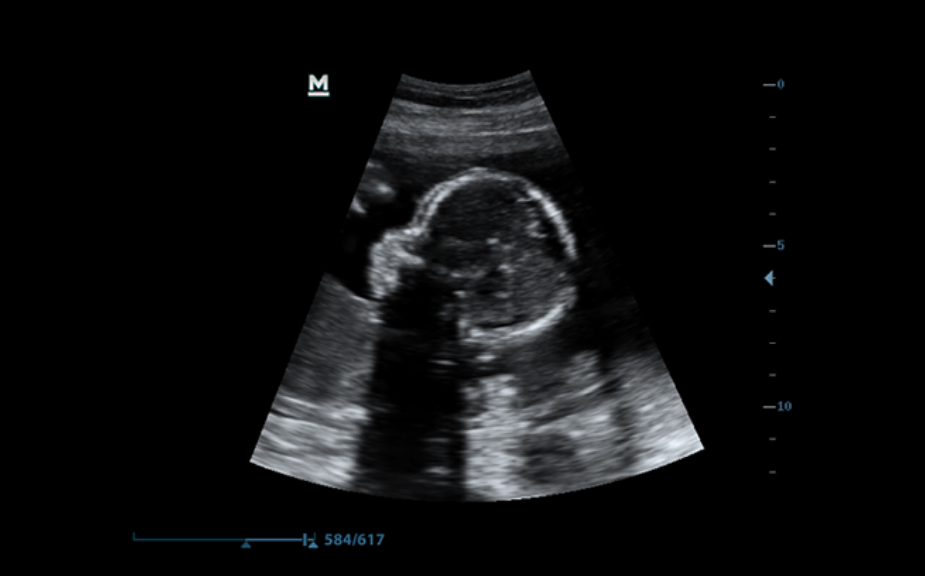

PSHTM (Faz Kaymal? Harmonik G?r├╝nt├╝leme)

M├╝kemmel ??z├╝n├╝rl├╝k ve daha az g├╝r├╝lt├╝ ile daha temiz g?r├╝nt├╝ler sa?layan daha iyi kontrast ??z├╝n├╝rl├╝?├╝ i?in saf Harmonik G?r├╝nt├╝leme.

3B/4B G?r├╝nt├╝leme

G?r├╝nt├╝n├╝n her y?nden h?zl? ve kolay bir ?ekilde izlenebilmesini sa?layan 3B/4B ?evirme ve E?itleme ?zelli?i ile